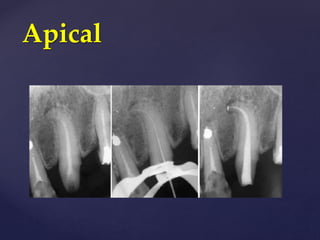

1. Apical

Apical

Apical Gauging

• The function of apical gauging is to measure the apical diameter of the canal

prior to cutting the final shape. This is necessary to ensure that the final tapered

preparation extends all the way to the terminus of the canal.